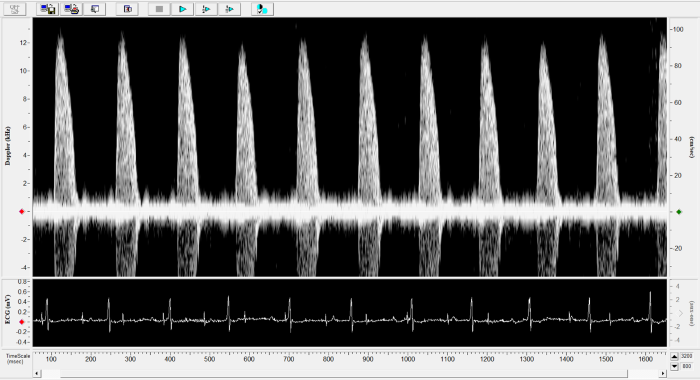

Mouse - Abdominal Aorta

Mouse - Abdominal Aorta. Image Credit: Scintica Instrumentation Inc.